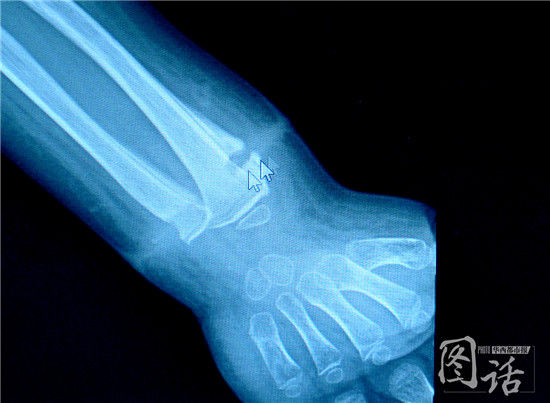

“手术过程中发现孩子手腕上有一根橡皮筋,已经长进肉里了,深深地嵌入骨膜表面。”符松说,为龙龙做脓液引流时,他发现伤口深处有一条白色物体,一拉还有弹性。取出后他看到,让龙龙手腕流脓的“罪魁祸首”竟然是一根直径不到2cm的橡皮筋!